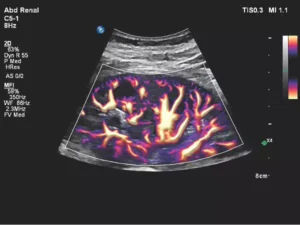

What is a Doppler:

A Doppler ultrasound is a non-invasive test that can be used to estimate the blood flow through your blood vessels by bouncing high-frequency sound waves (ultrasound) off circulating red blood cells. A regular ultrasound uses sound waves to produce images, but can’t show blood flow.

Colour Doppler Renal Arteries